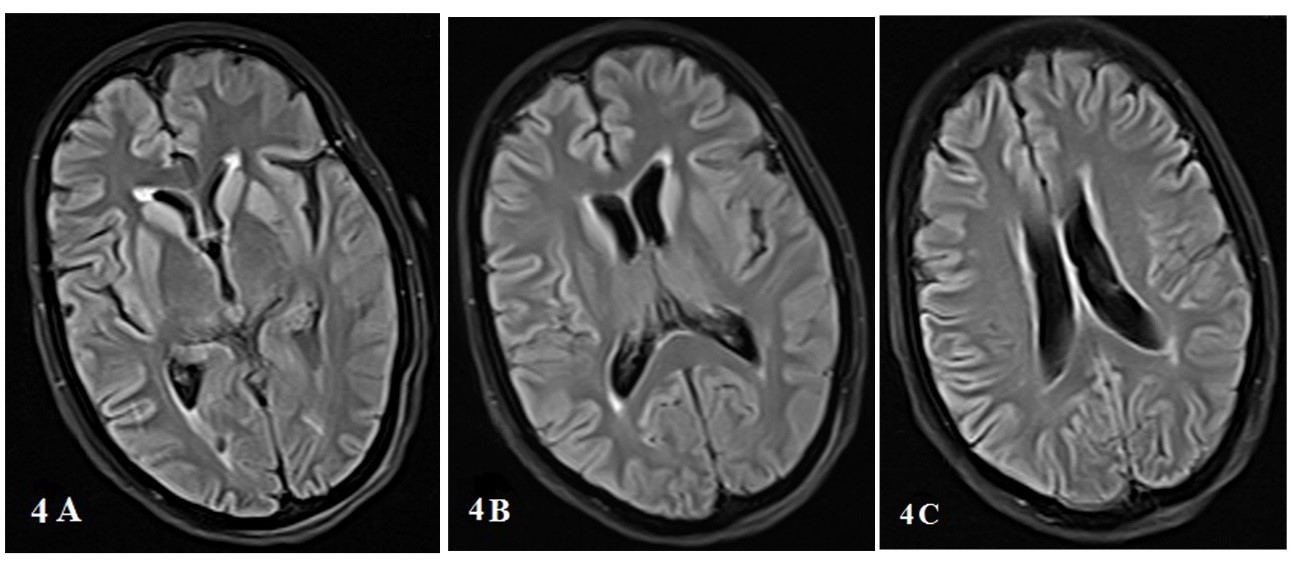

Background: Creutzfeldt-Jakob disease (CJD) is a progressive and fatal prion disease in human and its annual incidence is estimated one per million. Sporadic form of CJD is the most common form of the disease that involved 85% of cases. Case Report: We presented two cases of CJD with the different clinical presentation; a 58-year-old woman who referred with amnesia, depression and a 59-year-old woman with ataxia as her chief complaint. Based on the findings and roled-out the other differential diagnosis, the CJD was confirmed. Both of them died before 12 months after diagnosis. Conclusion: Although CJD is a rare disease with different clinical manifestation, it is considered as one the differential diagnosis of progressive dementia.[GMJ.2019;8:e1357]Â